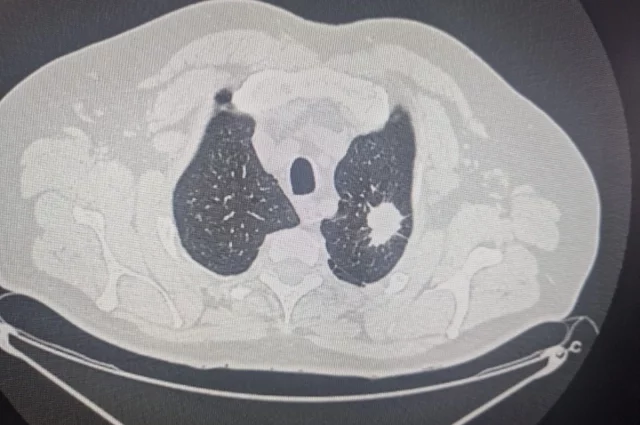

На конференции онкологов в Новосибирске обсудили проект создания референс‑центра с применением искусственного интеллекта. Предполагается, что он может помочь врачам в постановке диагнозов.

Ключевую роль в совершенствовании диагностики и лечения рака, по словам главного онколога региона Сергея Фурсова, играют методы с использованием низкодозных радиологических препаратов. При этом важнейшим инструментом становится искусственный интеллект.

«Нам предстоит организовать низкодозную компьютерную томографию. Искусственный интеллект необходим, потому что внедрение низкодозного скрининга и последующая расшифровка с двойным прочтением — это огромная работа, и обычных рентгенологов не хватит», — пояснил специалист.

Проект референс‑центра с ИИ призван повысить точность и скорость диагностики, что особенно важно при работе с такими массовыми онкологическими заболеваниями.